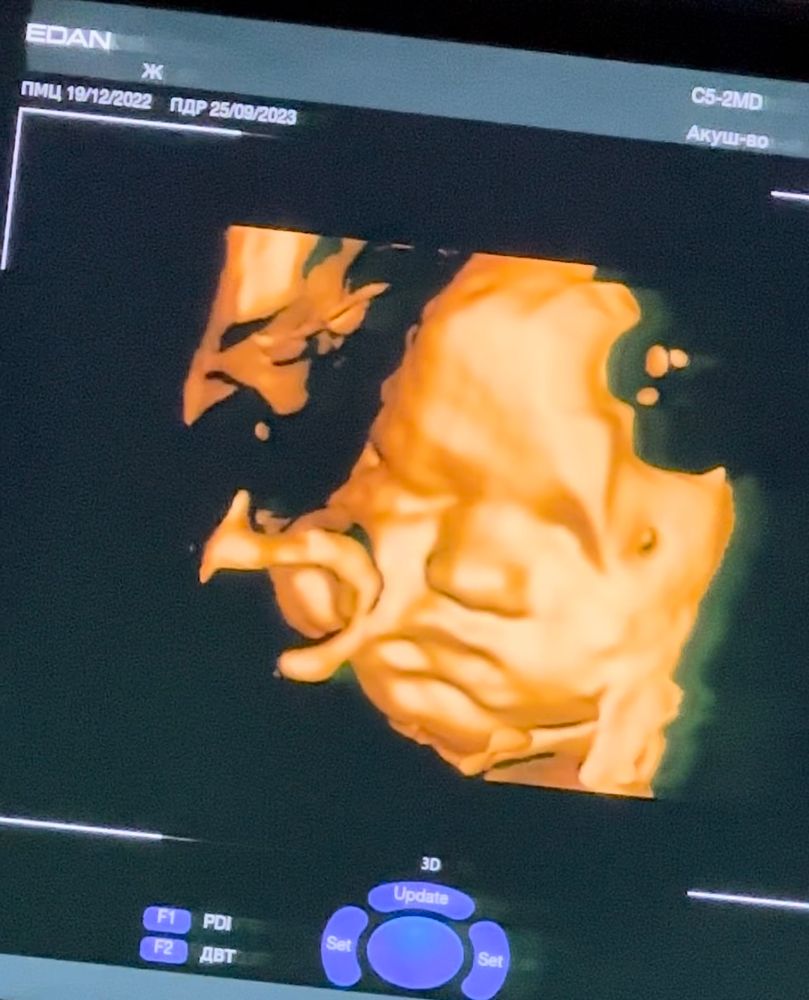

33 недели 4 дня

Были на УЗИ. Александра весит уже 2800 гр, по всем размерам опережает срок на 1,5 недели. Легла головой вниз, умница. Она в норме, я - в ремонте! 🤪 Сменила уже бригаду мастеров. Категоричности и решительности мне в эту беременность не занимать. Остается все меньше недель до встречи, а в голове все больше список незаконченных дел. Но для нее все готово. Даже накопитель для подгузников купила 😁 решила в этот раз испробовать.